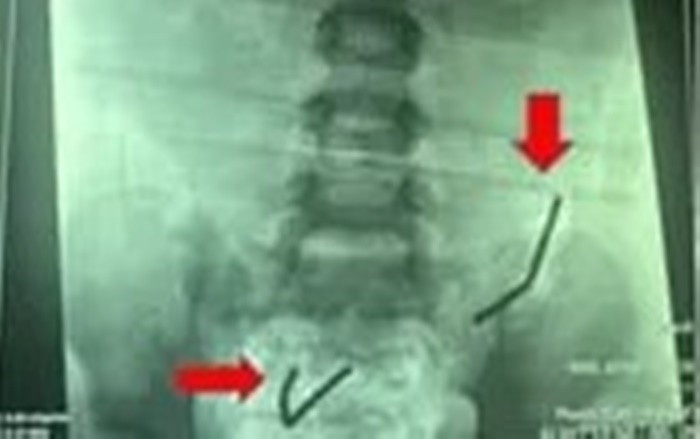

Khám lâm sàng ghi nhận bụng bệnh nhi có đề kháng, X-quang phát hiện dị vật xếp thành chuỗi trong ruột non. Siêu âm cho thấy viêm ruột và viêm phúc mạc. Các bác sĩ đã hội chẩn khẩn và tiến hành phẫu thuật nội soi.

Quá trình mổ, các bác sĩ phát hiện 2 chuỗi gồm 20 viên nam châm đã rỉ sét trong ruột bệnh nhi. Bệnh nhi bị thủng 8 lỗ ruột non, từ van hồi manh tràng lên trên 150cm, mỗi lỗ nhỏ đường kính 2 – 3mm, ruột bị tổn thương nghiêm trọng.

X-quang phát hiện dị vật xếp thành chuỗi trong ruột non/Ảnh VTV